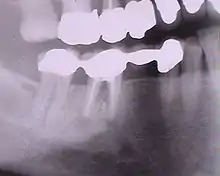

Bridge 3 éléments (dents nos 25, 26, 27)

Bridges

Un bridge (pont au Québec[3]) ou prothèse partielle fixe[1] permet de remplacer une dent absente, voire deux, en s'appuyant sur les dents adjacentes (une de chaque côté) ; au-delà le risque de fracture est trop élevé. Mais on peut également réaliser un bridge de plus grande portée, en prenant appui sur plusieurs dents piliers. Le principe est le même que pour la couronne.